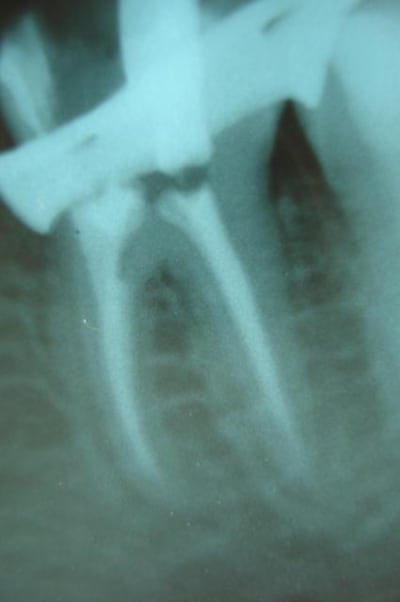

(mes photos : radio ortho et excentrée, "vue de dessus", tenons de chez Anthogyr, mordançage et tenon, et malheur de malheur pas de photo du résultat car plus de batterie dans ce satané appareil.=

Tes radios sont floues et la teinte étrange.

Canaux mésiaux semble avoir été un poil trop ouverts.

La racine mésiale semble mince

Bravo à Cingulum, il s'agit bien d'argentique photographié.

Désolé pour la qualité des radios, je sais que l'iconographie est importante.